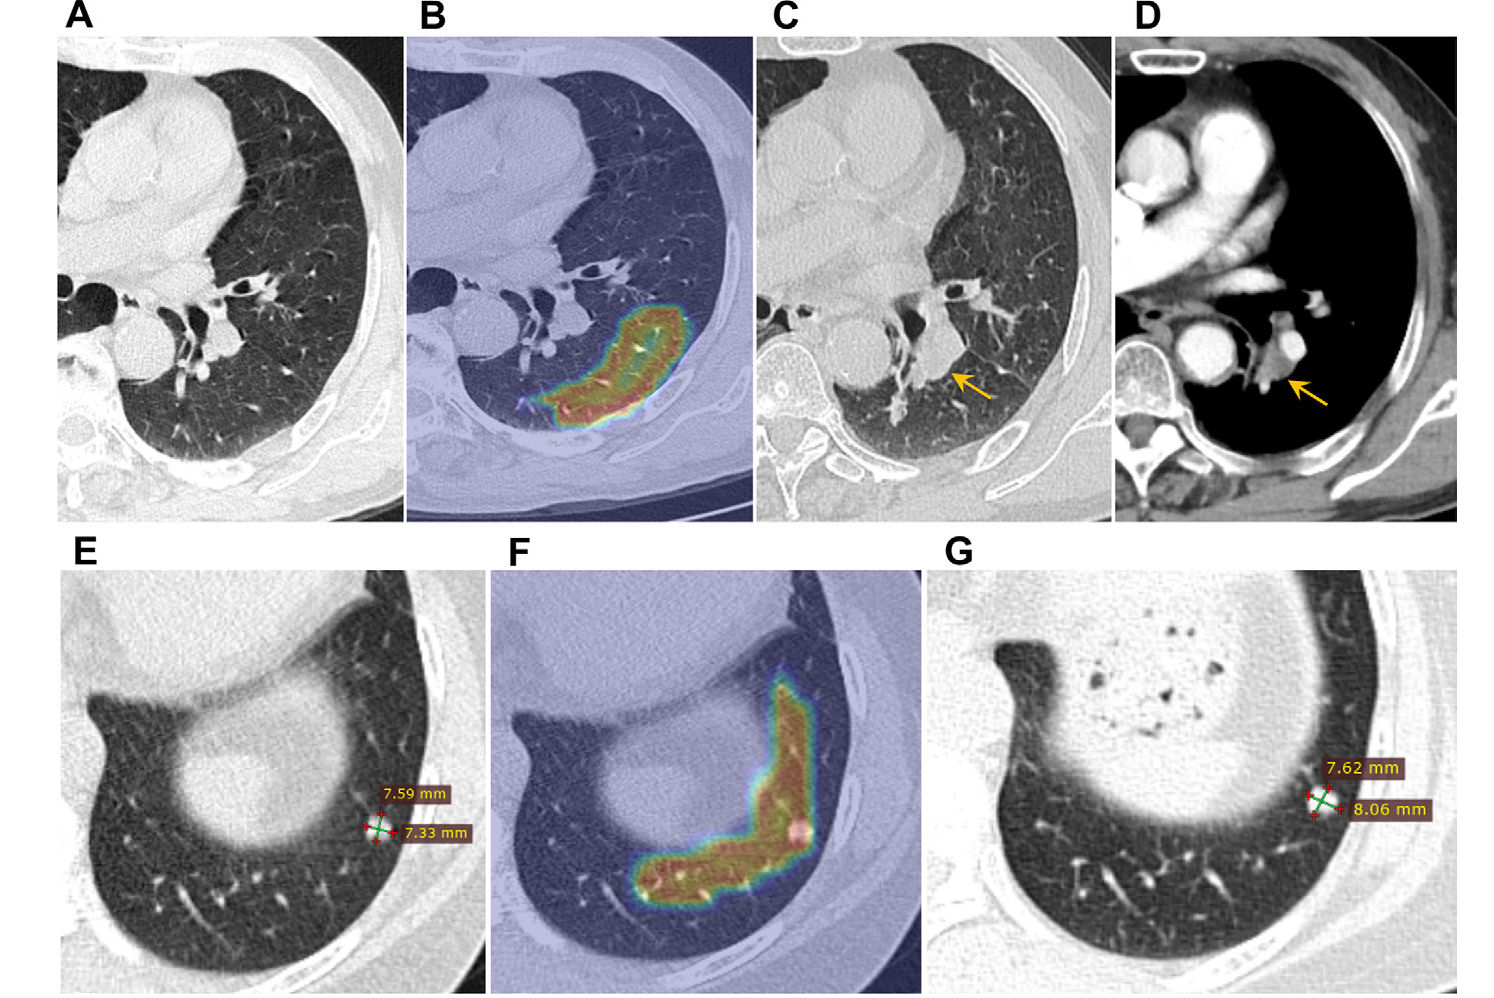

53-year-old woman with pure ground-glass nodule, diagnosed postoperatively as minimally invasive adenocarcinoma. Left panel shows source axial image with total nodule and solid component measured; middle shows segmentation of nodule on single slice; right shows habitats. CTR is 0, given absence of solid component. Habitats 1, 2, 3, and 4 have volumes of 921.8, 374.4, 45.1, and 0 mm³; and volume ratios of 68.7%, 27.9%, 3.4%, and 0%, respectively.Images and caption courtesy of the AJR.